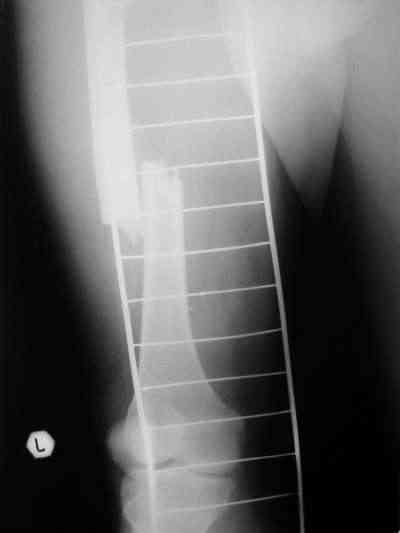

Около 10 дней назад выполнил остеосинтез бедренной кости LC-DCP и DHS по поводу фрагментарного оскольчатого перелома в средней трети и чрезвертельного перелома.

Снимки в приложении.

В приложении и имеющийся в наличии брейс. Приношу извинения за низкое качество снимков.

Качество снимков приемлемое. С нагрузкой категорически не надо спешить - только при уверенных рентгенологических признаках сращения на обоих уровнях в данном случае. Т.е. не только на диафизе, но и в вертельной области. При безупречном синтезе DHS ранняя нагрузка в этой зоне была бы безопасна, все определялось бы сращением диафиза. А поскольку винт в DHS сделали ну о-очень короткий, то ойкнуть не успеете, как

проксимальный отдел бедра в варус кувыркнется.

Глубокоуважаемый Никита!На бедре стоило бы обязательно провести межфрагментарный стягивающий винт и предварительно надо бы слегка изогнуть пластину,ну и может быть трансплантат по внутренней поверхности.А параллельно большому винту DHS провести спонгиозный винт для ротационной стабильности.Так,что с нагрузкой не нада тараписся!

Алексей Семенистый 28 Июль 2006, 20:08

Уважаемый Никита, очень меня расстроило не качество снимков, а сам остеосинтез. Вертельный перелом, пожалуй, еще срастется. А диафиз может преподнести ожидаемое, предуготованное осложнение: несращение и перелом импланта, даже если это суперфмрменная пластина.:(